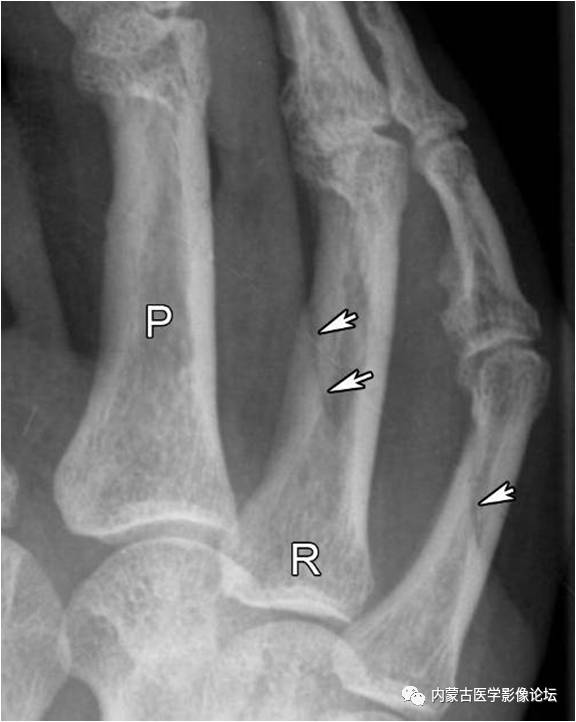

指骨滋养血管:箭头所示斜行透亮线影为近节指骨滋养血管,而白箭所示小圆形透亮区为中节指骨滋养血管轴位投照所致。注意指骨滋养血管从近端斜向远端,从骨皮质斜行走向髓腔,与掌骨相反。R:环指,P:近节指骨。

指骨Mach效应:箭头所示为环指(R)与小指骨结构内的软组织重叠影所形成的Mach效应,其走行与滋养血管影相反,也不应误为骨折线。